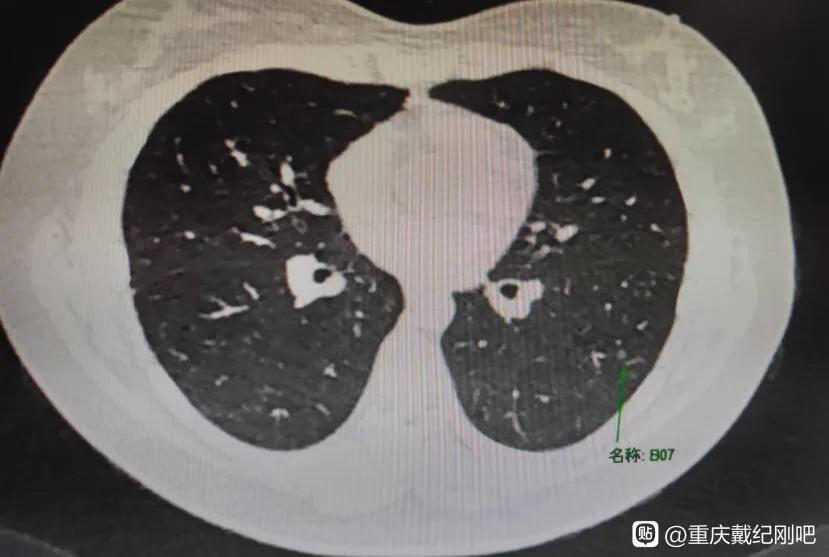

今天的这位也是这样,一个23岁,还在享受人生最好时光的小姑娘,因为长时间咳嗽就诊,查出双肺多发磨玻璃结节,最大的一个结节是9mm×6mm。小姑娘非常棒,不乱于心,不畏将来。自己已经茫然无措了,还可以很坚强的安慰着父母,然后独自面对所有压力。

然后9月2号做了增强CT,多发磨玻璃结节,右下叶磨玻璃结节0.9x0.6cm。医生看了报告说性质不定,很危险。听到我真的茫然无措,不知道怎么办了,开始不停百度,每天都休息不好,有时半夜还起来坐着发呆。从知道戴主任开始就一直一直没抢到号,最开始我还能安慰自己下一次,可是时间越长我越心慌。大家帮帮我吧,我想能不能去主任那里加号看一下。一边我还一直安慰我爸妈,一边自己一个人承受这些,做什么都是自己跑,真的好难受啊。另外很感谢热心的小哥教我怎样拍CT图,怎样贴吧发帖发图片。

9月6号小姑娘第一次在贴吧咨询,我建议:初次发现磨玻璃结节至少随访三个月后复查薄层CT,排除炎症后再精准诊断。若不消失,大的结节至少微浸润腺癌,小的至少原位,手术可根治。随后的面诊,我断定她的右肺结节是微浸润接近浸润了,最好是尽快手术治疗。因为她的这种情况我可以做到一次手术,解决所有有危险的肺结节,保全肺功能。这样一来小姑娘就可以安心的享受未来的美好的生活日子,不用纠结疾病的困扰。